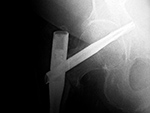

| 41 year-old man with chronic left femoral neck fracture and fracture of superior cannulated fixation screw. The partially visualized intramedullary nail is for an old femoral shaft fracture. |